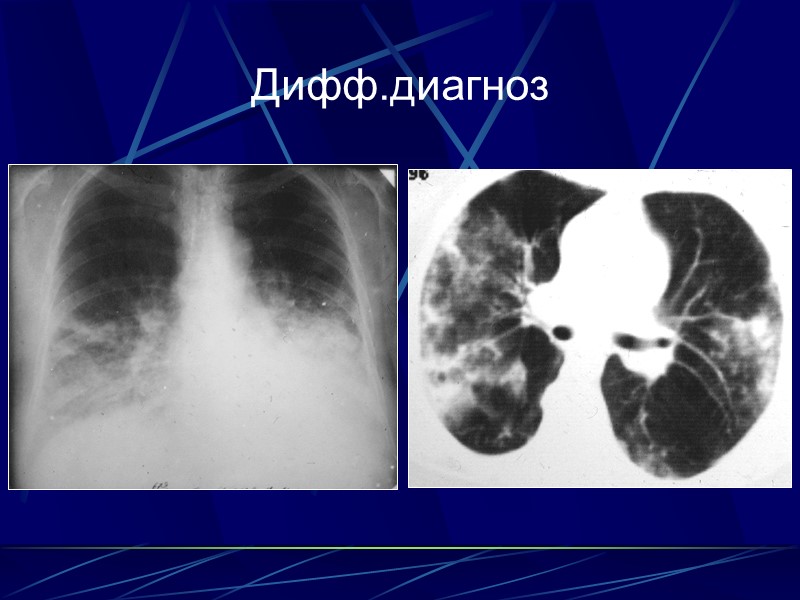

Дифф.диагноз

Дифф. диагноз